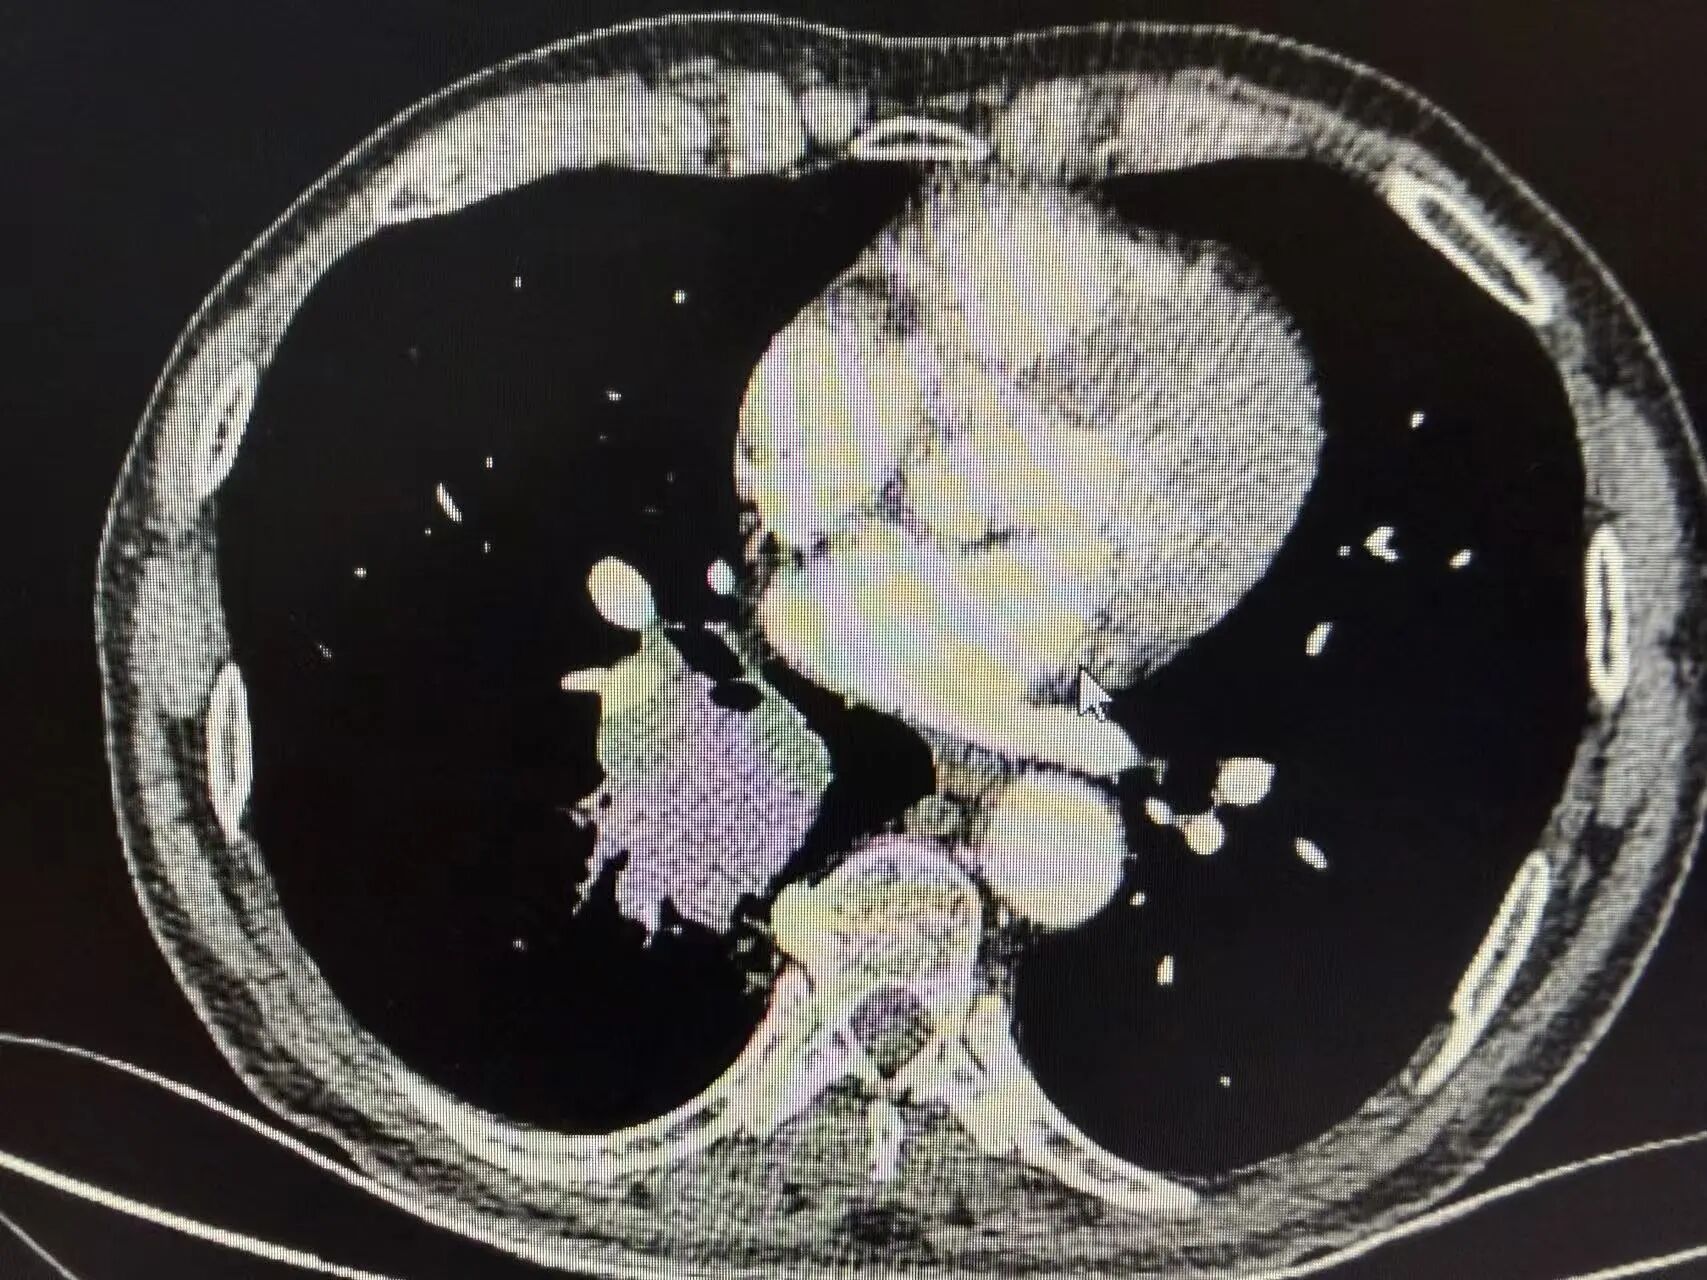

胸部CT:提示右下肺占位,病灶位置靠近肺门,已侵犯肺动脉,直接手术难度大、风险高。

治疗前胸片可见右肺门区域明显占位阴影,肿瘤体积较大,位置深、靠近中心大血管